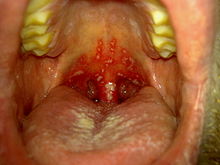

Herpetic stomatitis (herpetic gingivostomatitis)

This is inflammation of the mouth caused by herpes simplex virus.